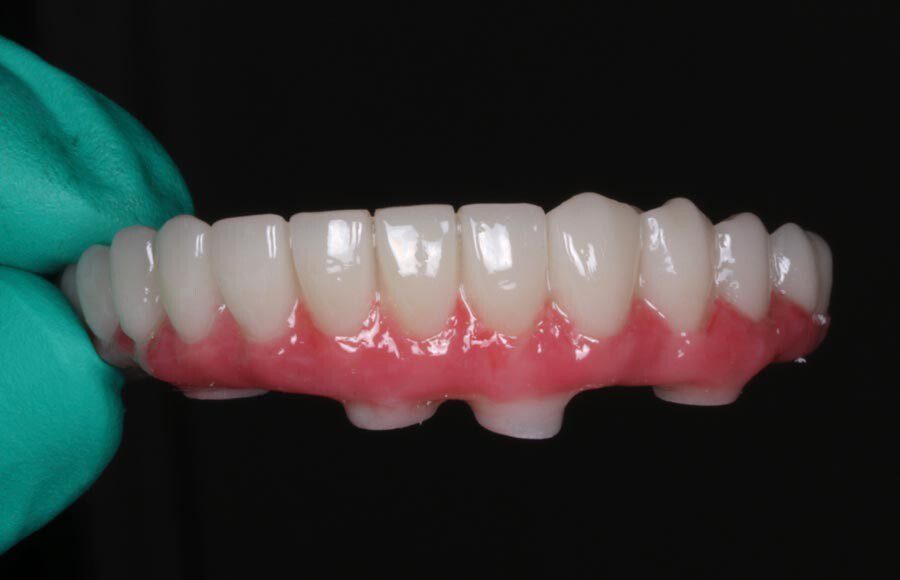

Smile GalleryImplant RestorationsImplant Dentures Post-op smiling 1 of 32 Pre-op close up smiling Pre-op lips retracted smiling Pre-op panoramic x-ray Implants in upper jaw (occlusal view) Implants in lower jaw (occlusal view) Panoramic x-ray of implants First set of try-ins – upper denture First set of try-ins – lower fixed provisional Delivered try-ins (lips retracted) Close adaptation to gums and appropriate emergence profile of lower fixed provisional Gum tissues have been molded by a convex provisional Delivered try-ins Second set of try-ins (lips retracted) Close adaptation to gums and appropriate emergence profile of second set of lower fixed provisional Delivered second try-ins Definitive restorations on casts (frontal view) Definitive restorations on cast (right side) Definitive restorations on cast (left side) Definitive upper overdenture (occlusal view) Definitive lower fixed titanium-acrylic hybrid restoration (occlusal view) Definitive lower fixed titanium-acrylic hybrid restoration (frontal view) Definitive lower fixed titanium-acrylic hybrid restoration (tissue side view) Healthy molded gum tissues on lower prior to delivery of lower fixed hybrid restoration Healthy gum tissues on upper prior to delivery of upper overdenture Definitive restorations (frontal, lips retracted) Definitive lower restoration (frontal) Definitive restorations (right side) Definitive restorations (left side) Definitive lower restoration (occlusal view) Definitive upper restoration (occlusal view) Post-op panoramic x-ray Post-op smiling